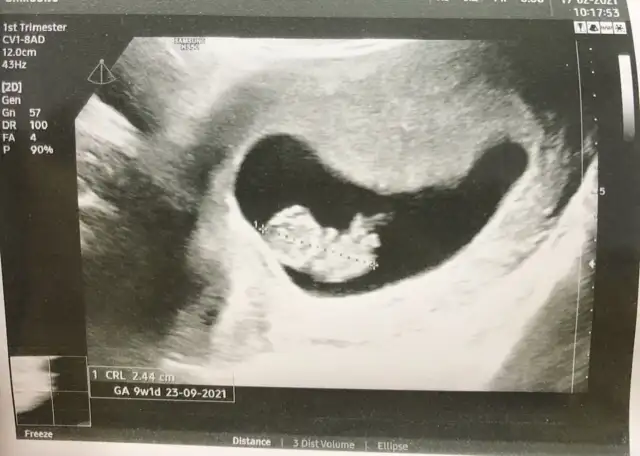

Kızlar birde nub teorisi mi var:emir_bebek: Bilenler bize de bir tahmin de bulunabilir mi:) 11+3 idik bir hafta önden gidiyormuşEki Görüntüle 2789737

Canım nub pek belli olmuyor gördüğüm o ise kız gibi 30 derece altında :)) yaa inşallah 12.hafta bende böyle bir şey görürüm bin kere maşallah canım. 💙